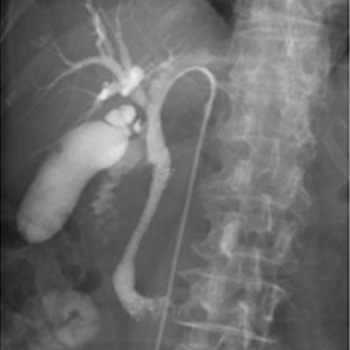

X線透視検査

X線をTVモニターに映像化し、リアルタイムの動画を見ながら検査や治療をおこなっています。バリウム検査や内視鏡検査、骨折整復などで使用しています。